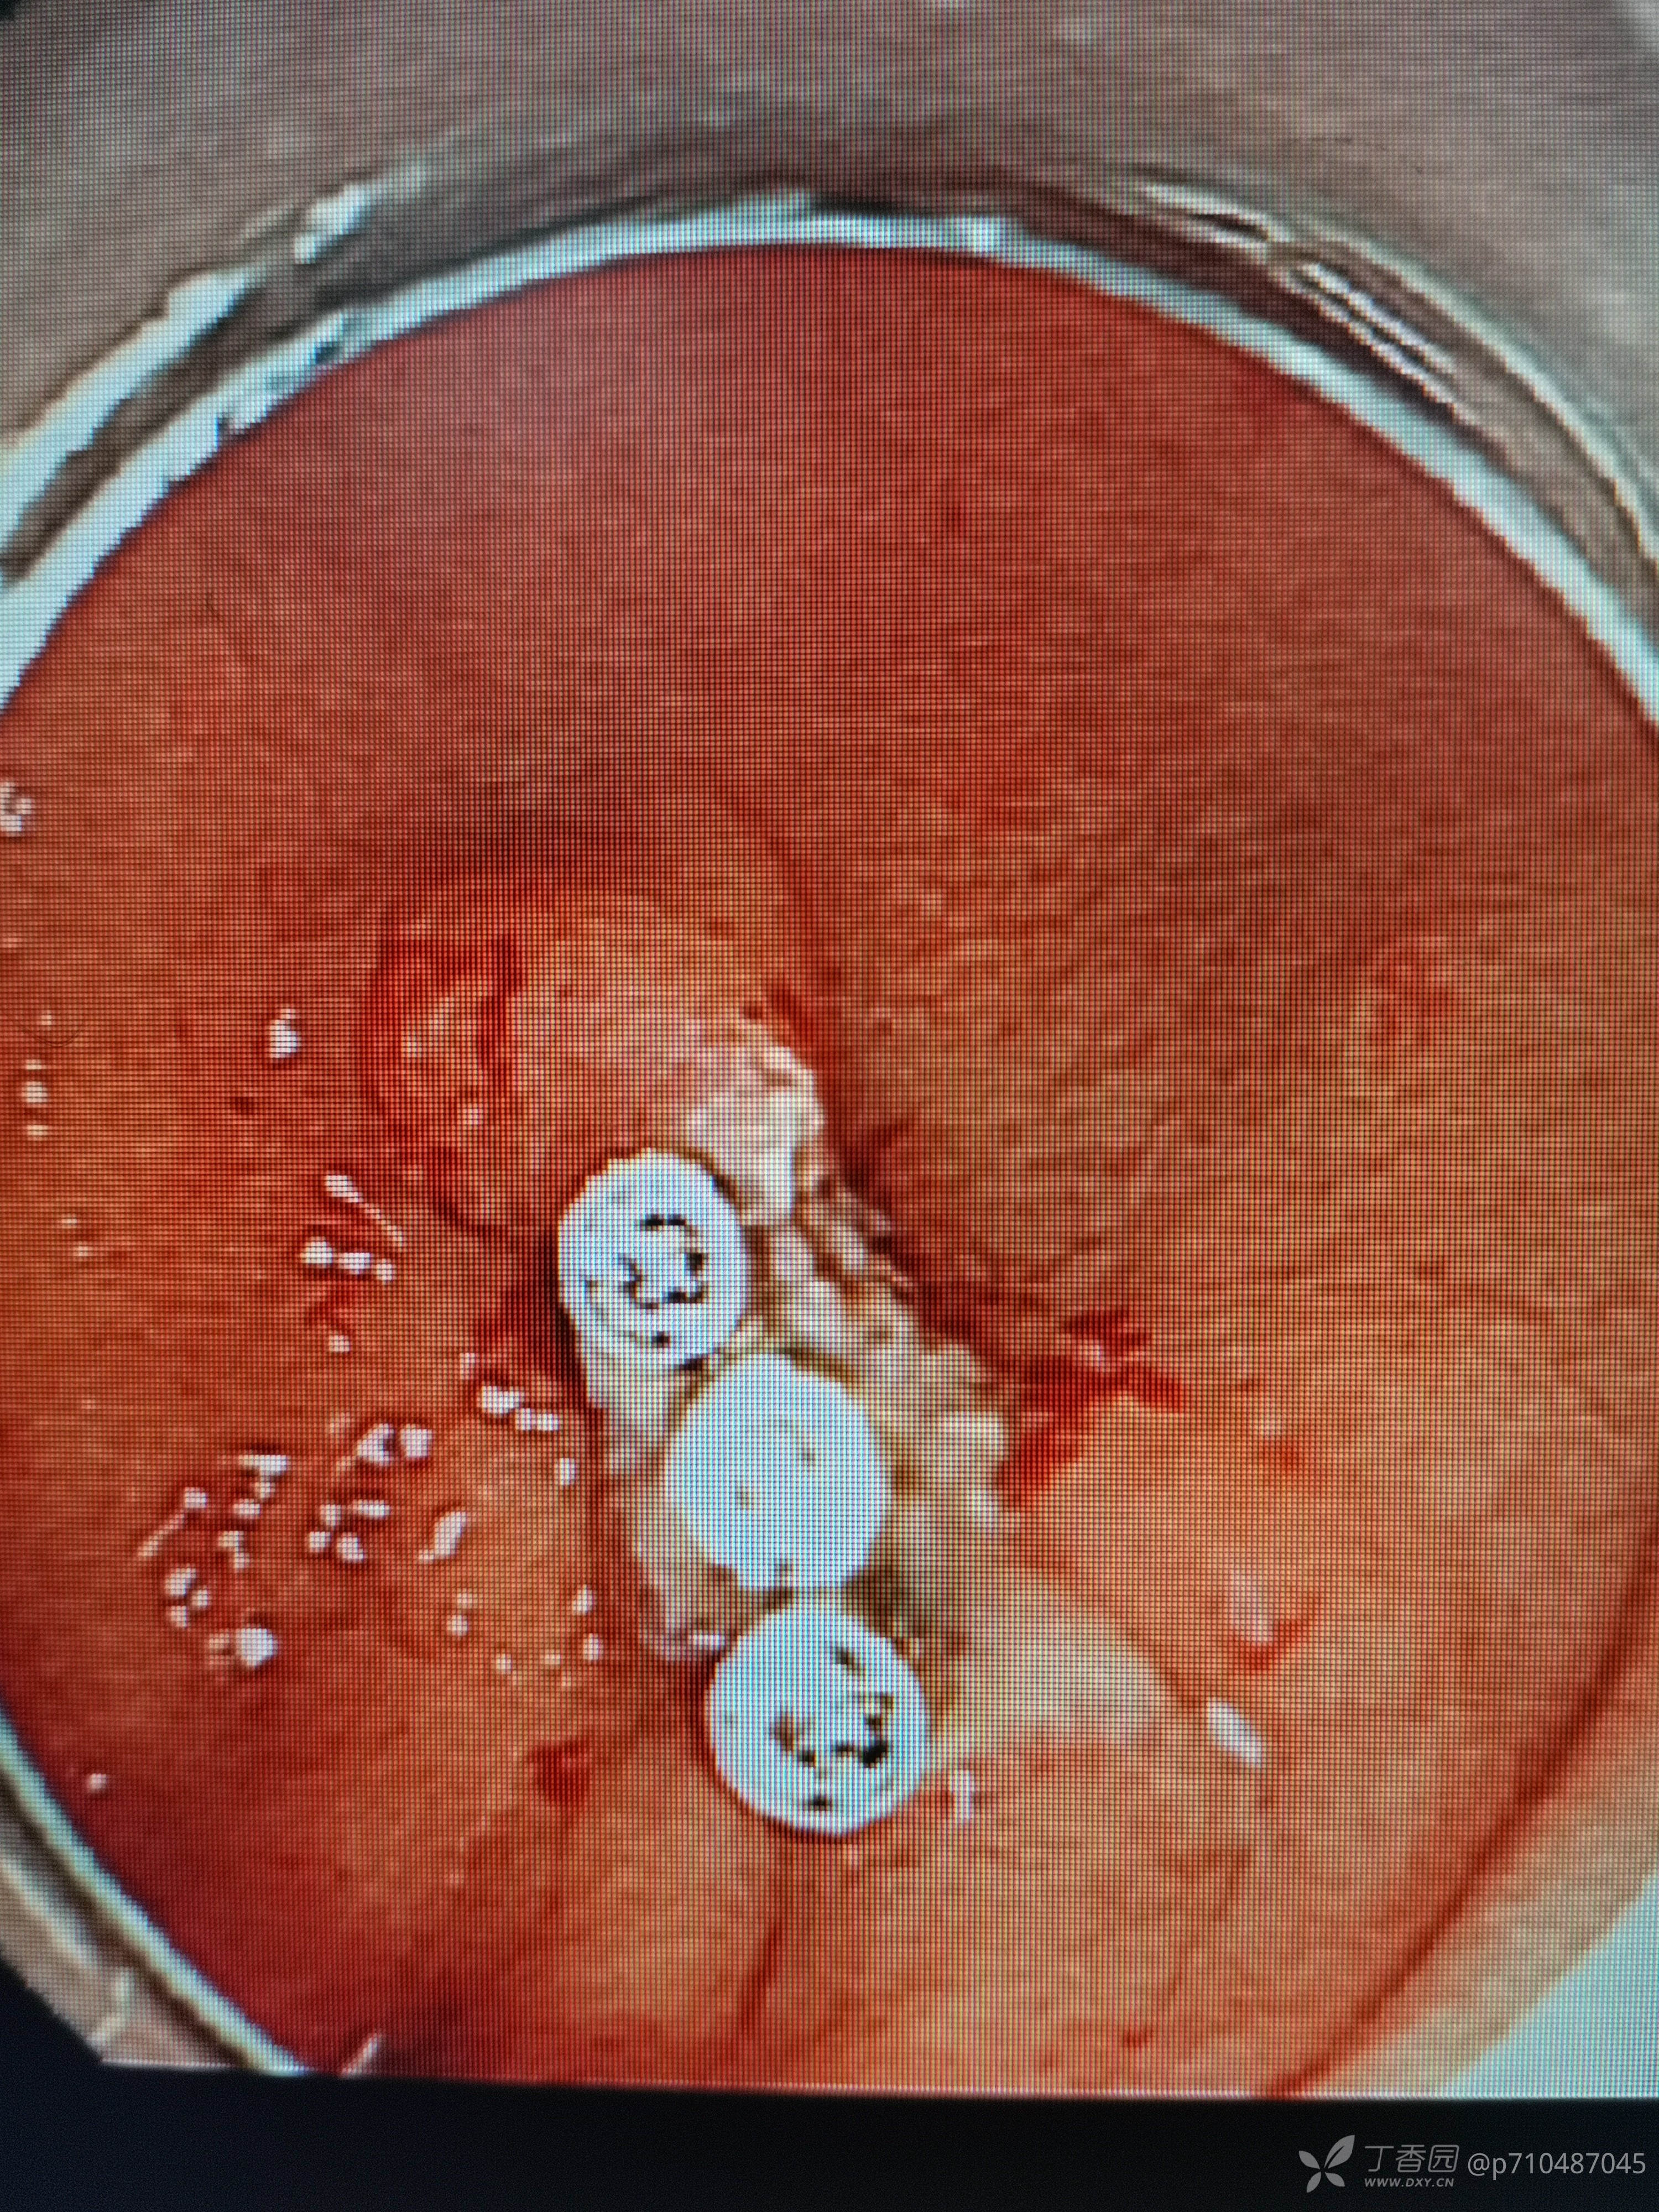

第二例六十余岁女性,胃体下部条状带蒂息肉行EMR术,主任亲自给我做助手,所以做的很顺利😁